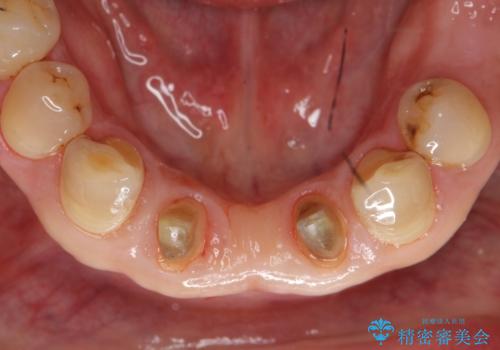

- 前歯のブリッジのやり替えをご希望されました。

かみ合わせが強く、以前入っていた保険治療のブリッジも前装が欠けてしまっていました。

セラミックも強い衝撃で欠けないわけではないため、強度のあるフルジルコニアクラウンでブリッジを作成しました。